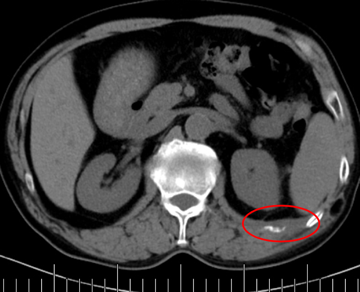

老年男性,68歲,肺癌術(shù)后肋骨轉(zhuǎn)移,痛疼難忍。

左側(cè)肋骨轉(zhuǎn)移

當(dāng)日痛疼緩解